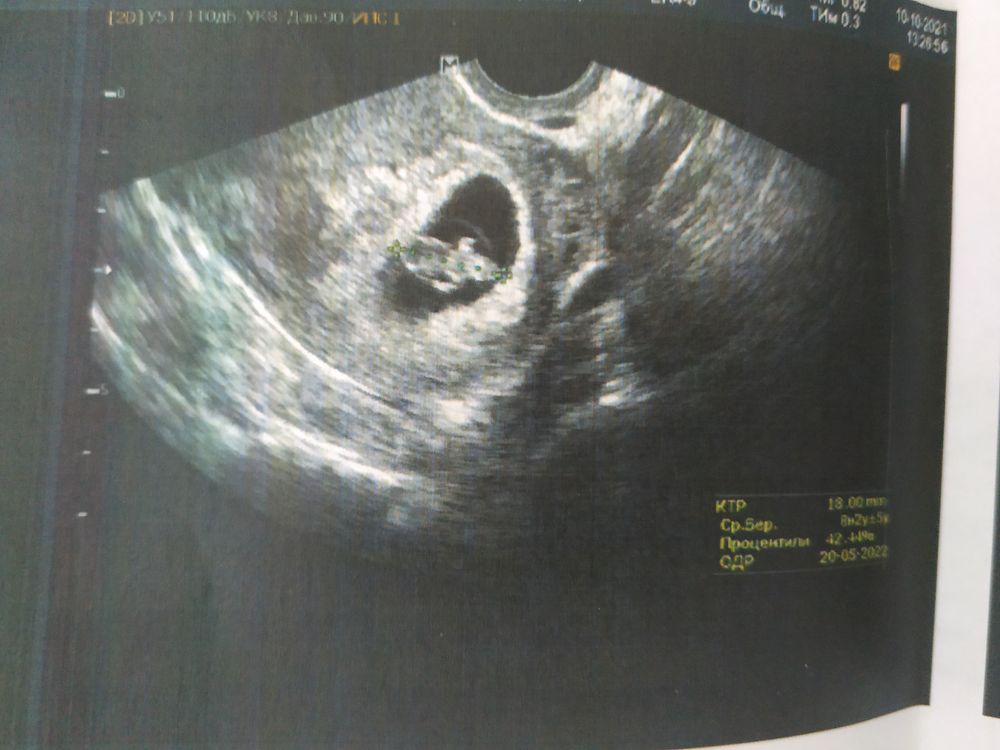

УЗИ, 8 недель

Сходили сегодня на первое УЗИ! По приложению и месячным срок 7 и 6 недель, но у меня после родов был гуляющий цикл, так что я не была уверена в сроках)) и вот, на УЗИ нам сказали, что по КТР срок 8 и 2. Все хорошо, ЧСС 169, лежит там такой человечек уже, с большой головой и ручками 😍❤️